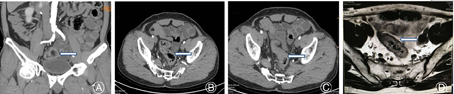

术中腹腔镜探查发现,降结肠沿左侧结肠旁沟下行至中段后开始向右侧移行,移行过腹正中线后向上行近横结肠水平,然后沿着升结肠平行、逆向下行至右侧盆腔移行为直肠(见封四,图2)。继续探查胃及十二指肠位置及形态正常,空肠与回肠无扭转,肝、脾位置正常。术中诊断为:右位乙状结肠解剖变异,低位直肠癌(T3N1M0)。明确变异解剖和诊断后,行直肠癌根治性TME术。因降结肠移行至右侧,形成异位乙状结肠,乙状结肠游离度小,长度短,为预防切除直肠肿瘤及肠管后,游离肠管的长度不够吻合,遂先行游离异位并行的降结肠,待游离完全后,提起乙状结肠系膜,游离显露肠系膜下动脉(Inferior mesenteric atery, IMA)和系膜下动脉静脉(Inferior mesenteric vein, IMV),发现降结肠、乙状结肠的血管供应也相应的变异于右侧,离断IMA和IMV。然后提起乙状结肠系膜,暴露并游离骶前筋膜,并沿骶前行隧道式分离,保护双侧腹下神经,分离达腹膜反折水平以下后,常规游离直肠后壁,游离至骶尾水平后,开始游离直肠前壁,在腹膜反折上0.5 cm处弧形切开腹膜,沿腹膜反折找到直肠前间隙,游离显露灰白光滑的Denonvilliers筋膜,暴露两侧精囊腺,沿两侧Holy界面打开直肠侧方组织,直肠后壁分离跨过肿瘤下缘达肛提肌裂孔边缘,在裂孔水平离断直肠,经耻骨上二横指取长5 cm纵行切口,取出直肠切除标本;乙状结肠近端放置29 mm吻合器钉头并固定,还纳入腹腔,封闭切口,将吻合器主体端自肛门置入,检查肠管无扭转后击发吻合器,完成吻合,吻合后肠管的紧张度适中,盆腔内注水做充气试验检测无漏气,检查无活动性出血,清点器械、辅料无误后完成手术。

本例中,术前没有明确发现患者是右位乙状结肠,术后重新阅片,与影像科专家讨论,结合手术中所见,明确发现盆腔CT与MRI中有显示乙状结肠位于患者右下腹(见封四,图3)。本例优势在于该患者行腹腔镜下直肠癌根治术,故腹腔镜探查时即发现乙状结肠位于患者右下腹,随即术者换位于对侧行手术游离,术者腹腔镜技术娴熟程度对于罕见病例手术的成功也有关键作用。TME由Heald等[9]于1982年首次提出,经过近20年的临床实践表明,TME术后直肠癌的术后复发明显减少,患者的5年生存率也明显改善。然而关于TME术中IMA的处理方式,目前绝大多数专家推崇高位结扎,即自腹主动脉发出后的IMA起始处结扎。本例中术中可见肠系膜下动脉转向右侧,并分出相应的左结肠动脉、乙状结肠动脉、直肠上动脉,遂从IMA根部结扎。术后病理示淋巴结检出11枚,均未见癌转移。术后患者未见吻合瘘且排便、排尿均正常。然而并不是所有的右位乙状结肠患者均存在同样的血管分支,例如在Indrajit等[10]研究中发现右位肠系膜下动脉向上发出右结肠动脉,向下分出降结肠动脉及直肠上动脉,因此对于此类右位乙状结肠合并结直肠肿瘤的患者,术中应仔细解剖各血管分支以免错误结扎血管并引起相应肠管的坏死。再者,术前也有必要通过血管造影的方法确定血管走行。此外,因右位降结肠、乙状结肠位置的特殊性,在行直肠肿瘤切除过程中,尽量多游离降结肠及横结肠,避免术后肠管形成折角导致术后肠梗阻。